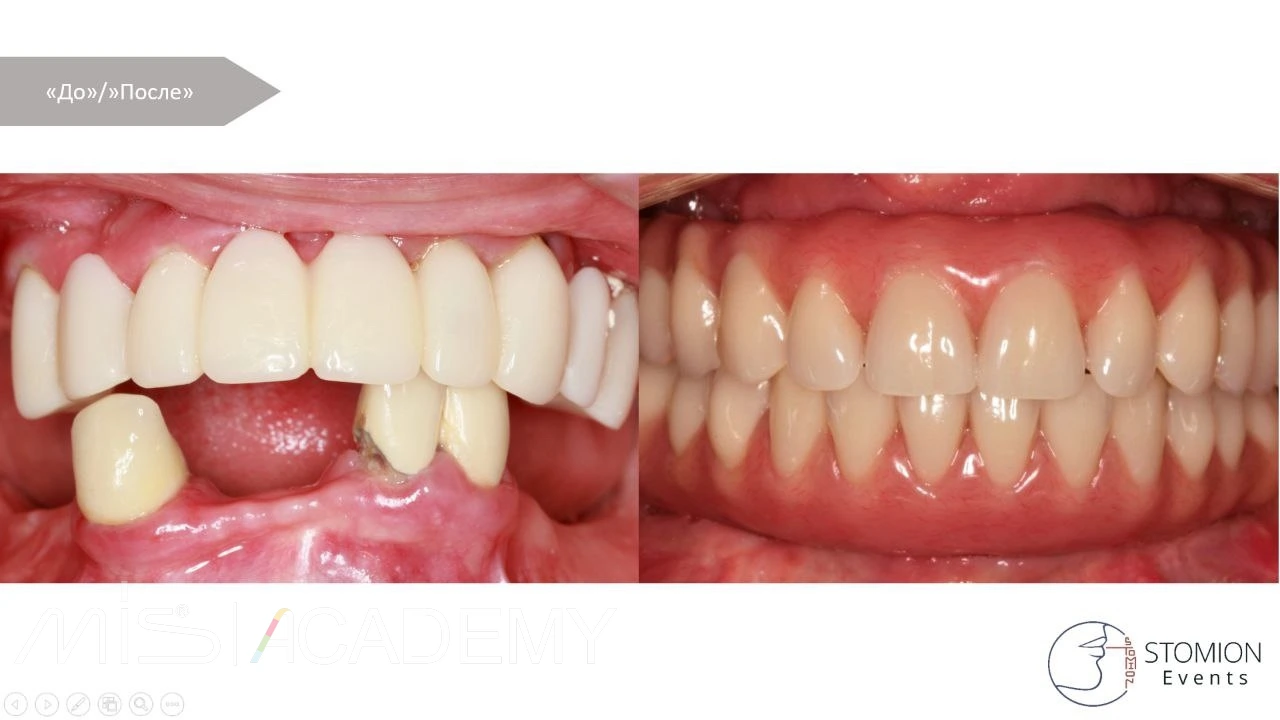

P/S На финишном фото — акрил с КХС. Вроде выглядит неплохо. Хотя мы сейчас предпочитаем делать на титановой балке, чтобы контакт слизистой был с полированным титаном, а не акрилом.